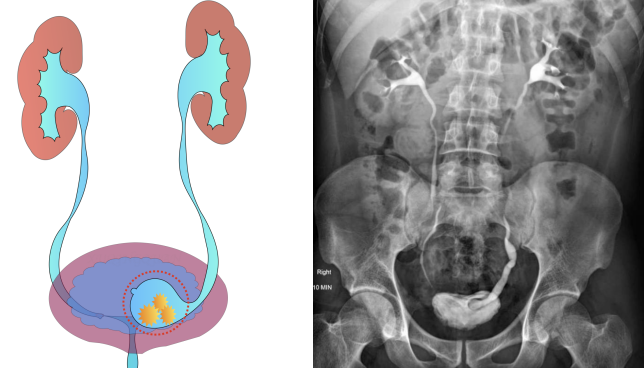

(2)输尿管结石

输尿管结石长期嵌顿可刺激输尿管黏膜,引起炎症和纤维组织增生,导致输尿管狭窄。

(2)静脉肾盂造影(IVP)

IVP 可显示输尿管的形态、狭窄部位和程度,以及肾脏的功能,但对于严重肾积水或肾功能不全的患者,造影剂排泄不佳,可能影响诊断效果。

CTU 是目前诊断输尿管狭窄的重要方法,能清晰显示输尿管的全程形态、狭窄部位、长度、周围组织的关系以及肾脏的结构和功能,对于制定治疗方案具有重要意义。

有研究[6]表明,CTU 对输尿管狭窄的诊断准确率可达 90%以上。